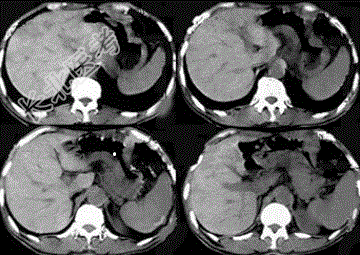

- 单项选择题男性,50岁, 中上腹饱胀、疼痛半年,消瘦, CT扫描如图,应诊断为

A、淋巴瘤

B、胃腺瘤

C、胃癌

D、胃窦溃疡梗阻

E、胃平滑肌瘤